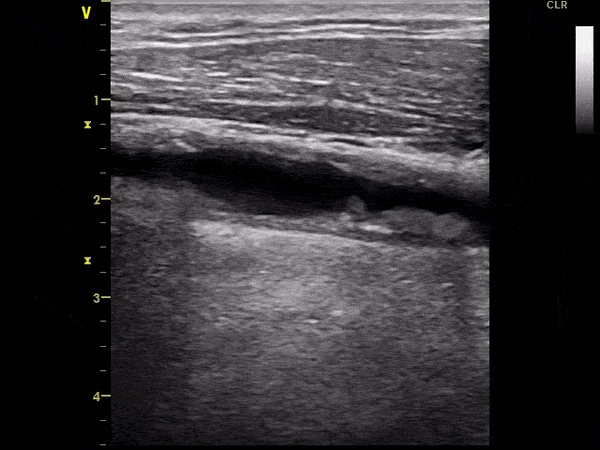

Ekografi e vazave të qafës

Ekografi e arterieve karotide dhe e arterieve vertebrale triplex (2D, color, doppler). Me anë të këtij ekzaminimi:

• Shihet pllaka arteriosklerotike.

• Përcaktohet përqindja e ngushtimit të arteries karotide.

• Përcaktohet forma, gjatësia dhe vendndodhja e saktë.

• Përcaktohet lloji i pllakës arteriosklerotike. Nëse është e butë, e çrregullt, jo e kufizuar mirë nga kapsula e saj – ajo mund të çahet dhe të shkaktojë insult cerebral trombotik.

Pamje të kapura me ekografi të vazave të qafës: